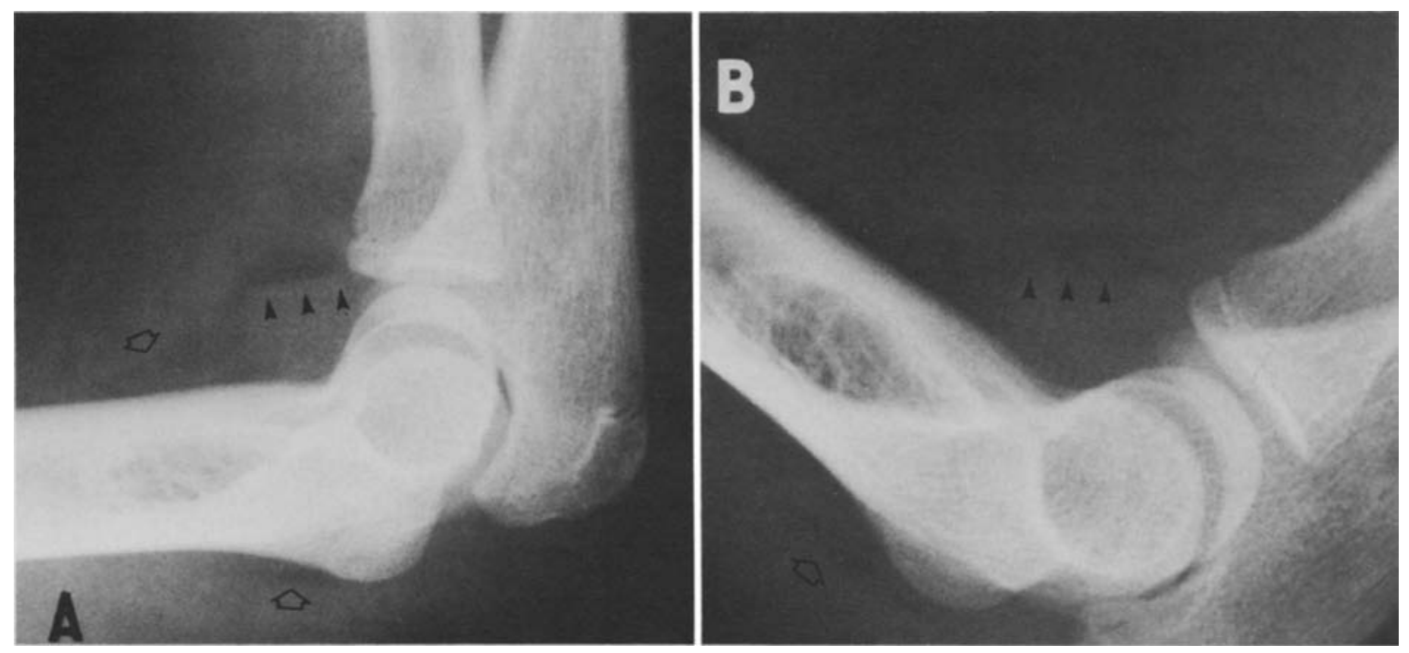

肘关节积脂血症与肘关节脂肪垫征原理类似,在肘关节骨折后关节腔内积血将肘关节脂肪垫抬高,高度提示桡骨小头骨折。

病例7 一例10岁患者肘关节外伤,侧位可见明显关节积脂血症。